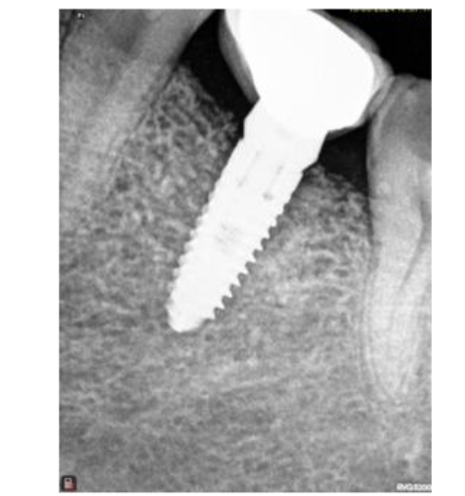

After a period of 5-month showing intraorally and radiographically the site from where bone core using trephine was taken for histological analysis; the same site where implant, Mis implant 3.75/11.5 was placed.

All sites healed uneventfully. There was no sign of post-operative infection. None of the patients showed any complications post-surgical. Additionally, none of the surgical sites needed additional hard or soft tissue grafting. Upon implant placement, the surgical sites showed appropriate healing as it is seen in any other grafted areas. Furthermore, there was adequate bucco-lingual width of the grafted for Implants placement. Implants placed showed satisfactory primary stability.